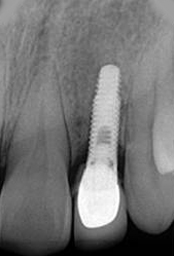

X-ray of Implant

Single Tooth Implant

Placement of Bone Grafting